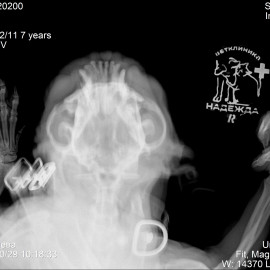

В другой клинике был поставлен диагноз: перелом тела нижней челюсти правой и левой стороны. Была проведена операция: остеосинтез нижней челюсти.

Снимок 1-2 до операции.